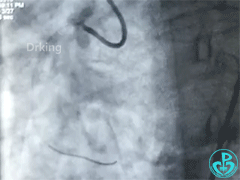

76岁女性,不稳定型心绞痛,PCI。

RCA病变:

桡动脉痉挛,股动脉钙化迂曲,使用泥鳅导丝,造影于右冠植入支架。